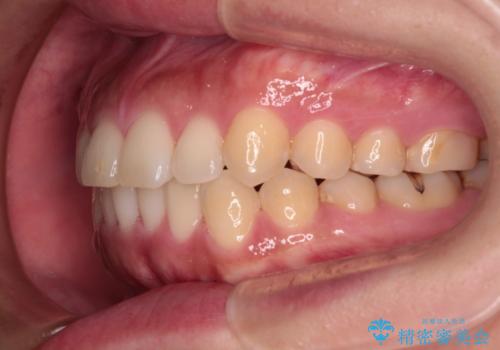

【モニター】カリエール・ディスタライザーを併用した八重歯のインビザライン矯正

- 前歯の叢生と八重歯を気にして来院された患者様です。

目立たない装置を希望とのことで、インビザラインにて矯正治療を行うこととしました。

インビザライン単体で改善することも可能ですが、八重歯とその後方にある歯列を確実移動させないと、上下正中がずれてしまう可能性があります。

インビザライン単体での治療ではなく、カリエール・ディスタライザーという補助装置を併用して、より確実性を上げることとしました。

補助装置で八重歯を解消しながら、並行してインビザラインで歯列を整えることとしました。

カリエールディスタライザーを併用したことで、すっきりとした口元になり、上下の正中を合わせることができました。